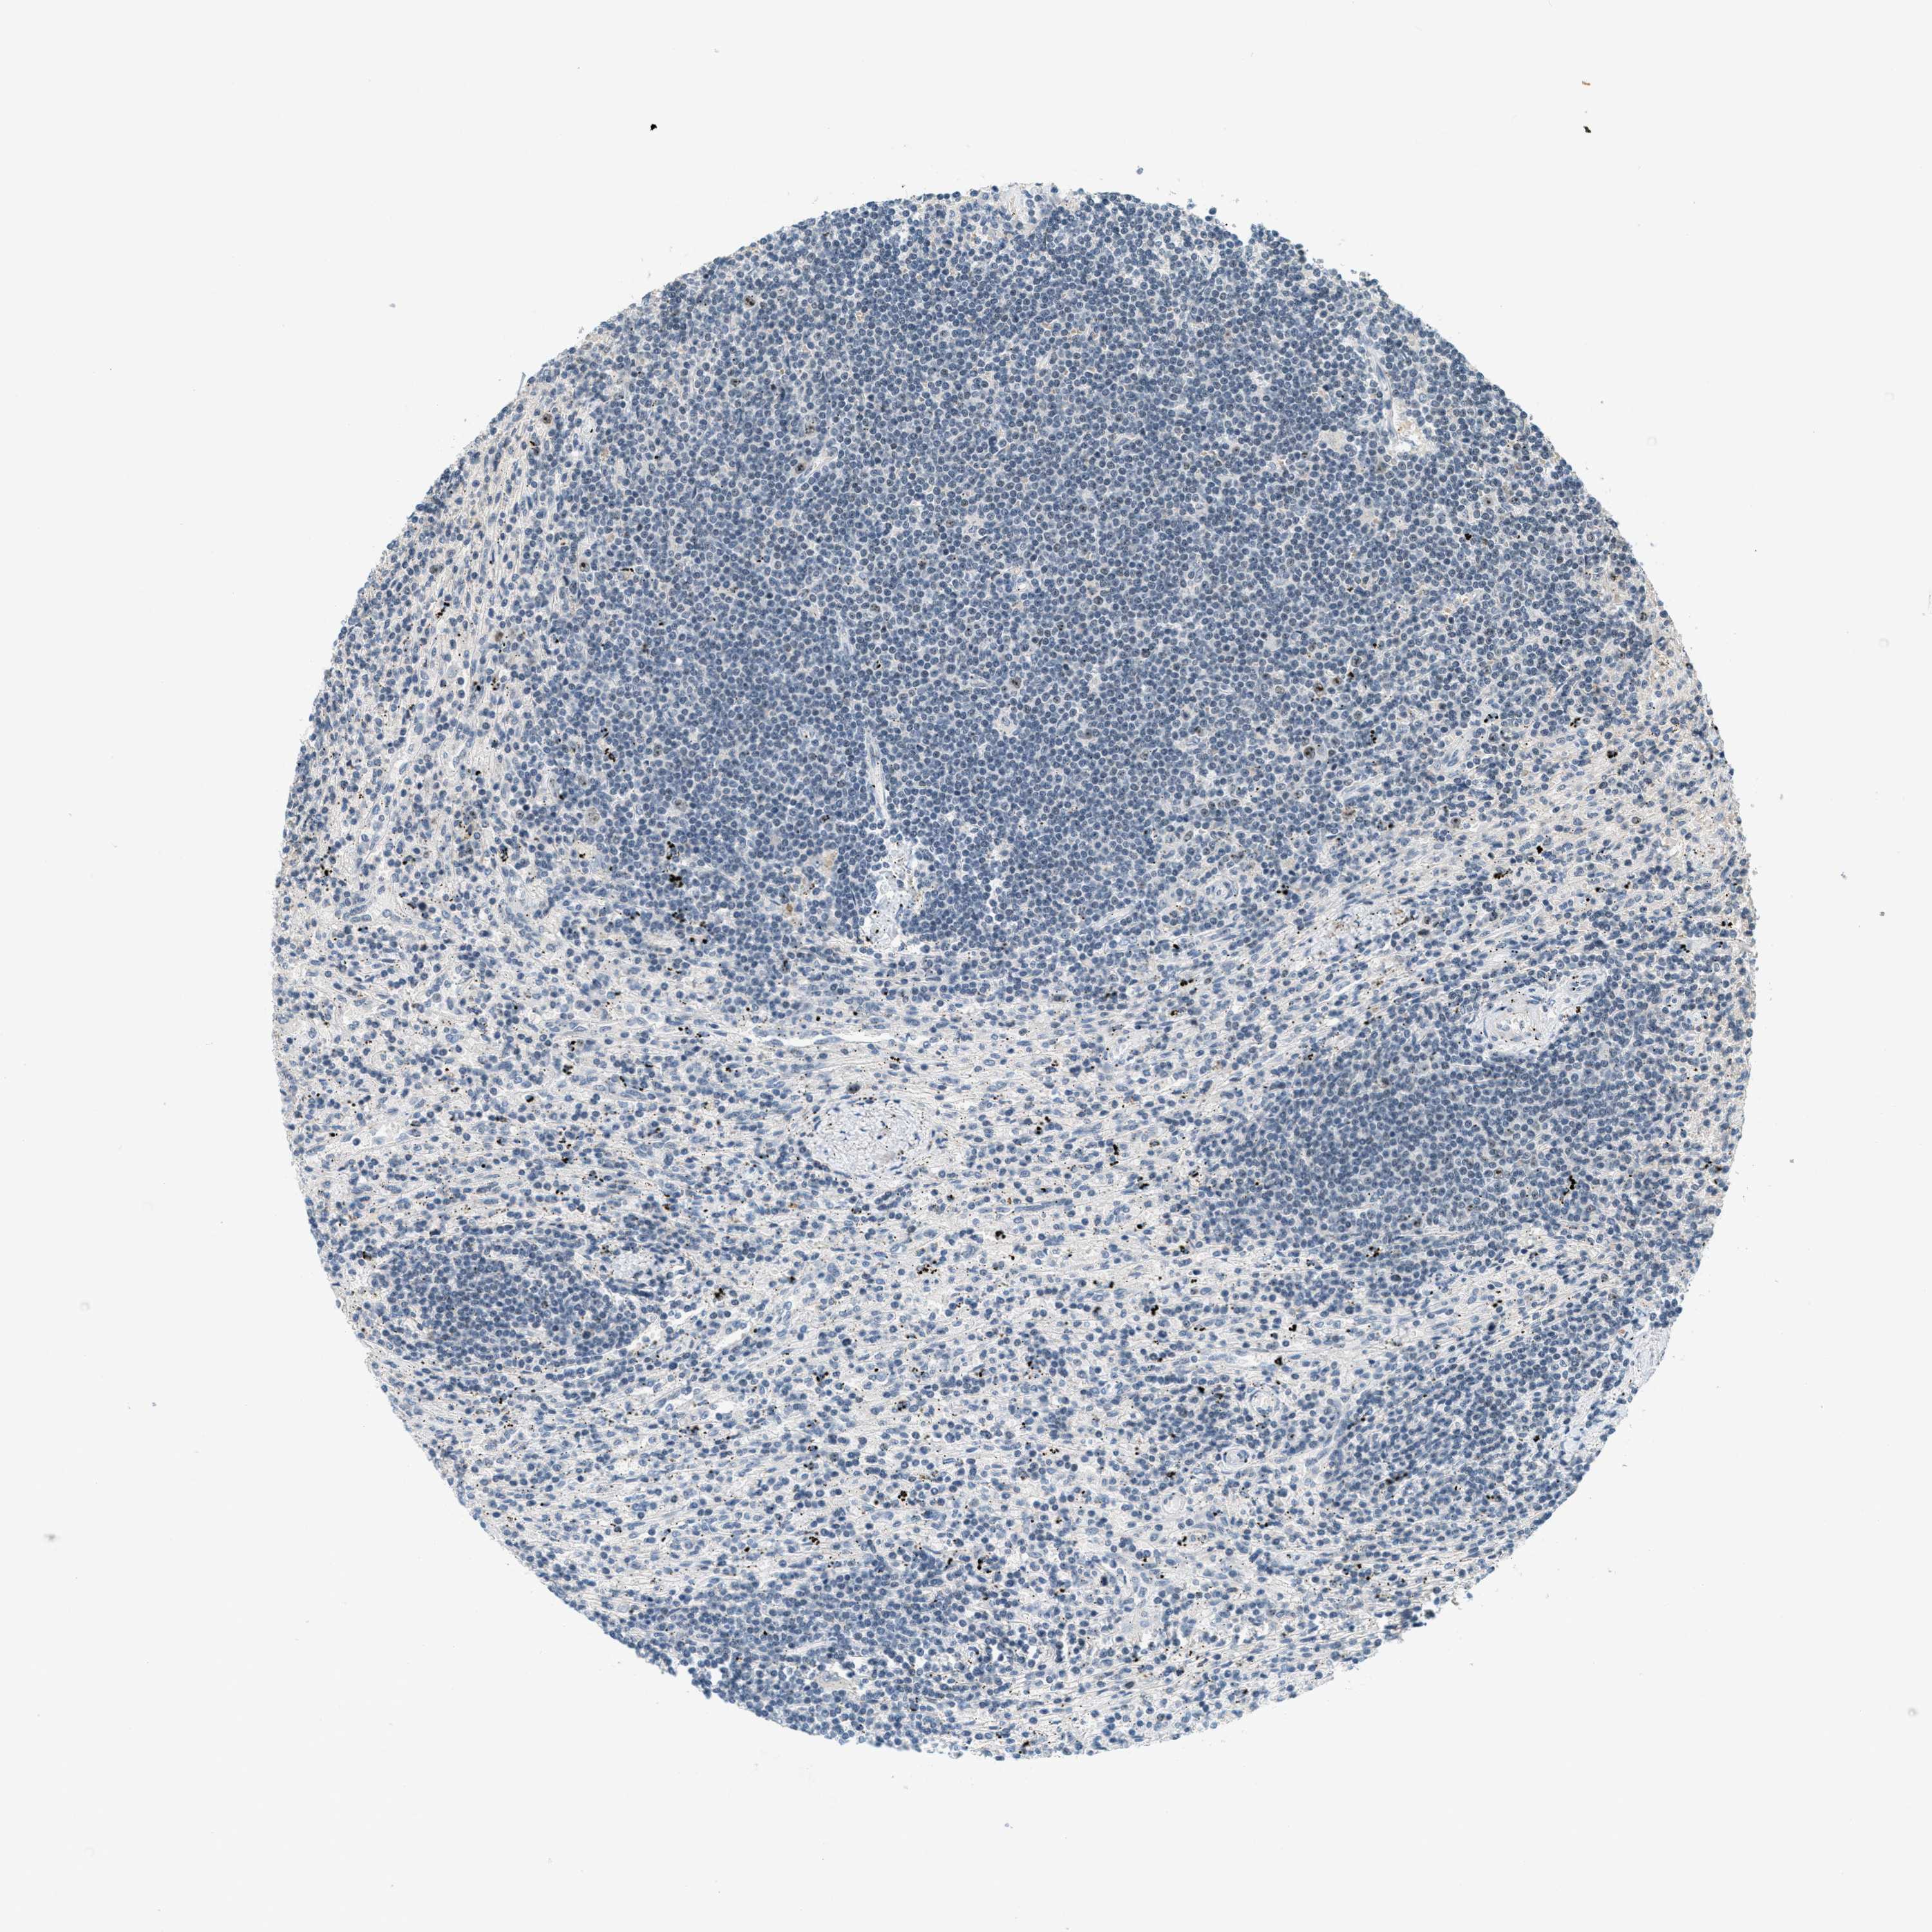

CANCER LYMPHOMA Show tissue menu

LYMPHOMA - Protein expressioni

A mouse-over function shows sample information and annotation data. Click on an image to view it in a full screen mode. Samples can be filtered based on level of antibody staining by selecting one or several of the following categories: high, medium, low and not detected. The assay and annotation is described here.

Each image is clickable and will lead to virtual microscopy that enables deeper exploration of all samples and also displays staining intensity scores, fraction scores and subcellular localization as well as patient and tissue information for each sample.

Antibody HPA014855

Staining

High

Medium

Low

Not detected

Intensity

Strong

Moderate

Weak

Negative

Quantity

>75%

75%-25%

<25%

None

Location

Nuclear

Cytoplasmic/membranous

Cytoplasmic/membranous,nuclear

Hodgkin's disease, NOS

Malignant lymphoma, non-Hodgkin's type, High grade

Malignant lymphoma, non-Hodgkin's type, Low grade